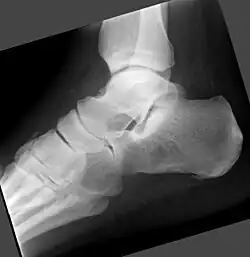

- Fuß, Röntgen

-

Vorhandenes Knochenmarködem nicht erkennbar